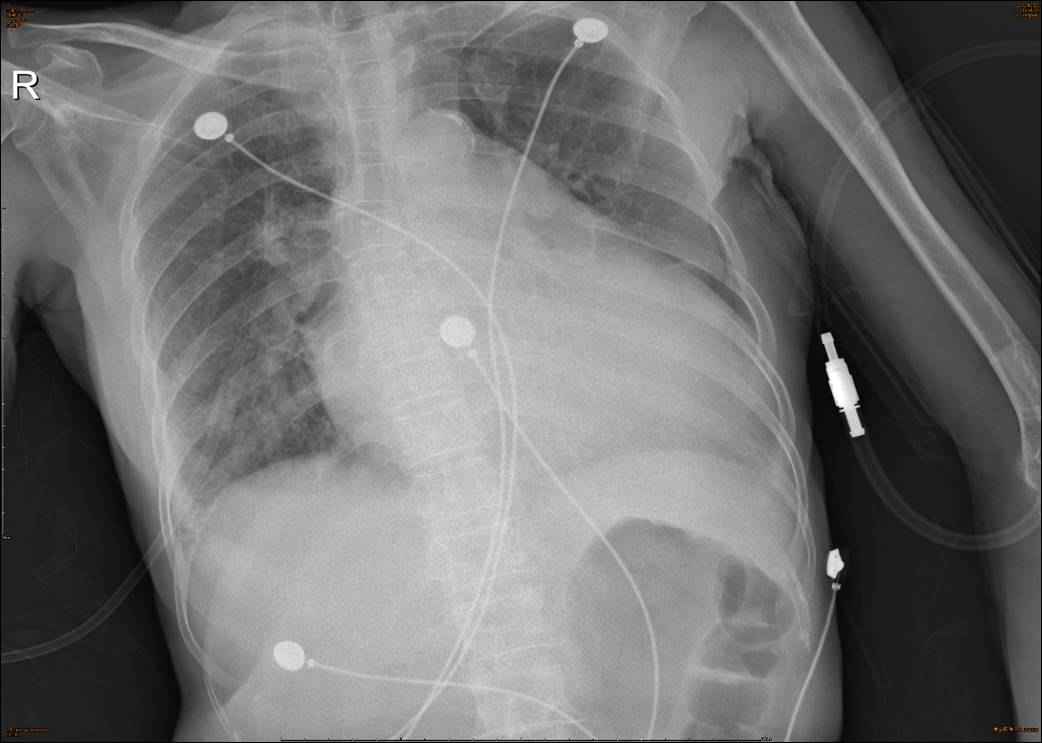

【胸片】:

♦影像描述: 所示胸廓骨骼及胸壁软组织未见异常。纵隔及气管居中未见移位。

♦纵隔未见增宽。

♦心影明显增大,主动脉壁钙化。

♦两膈光整,右肋膈角欠清,左肋膈角变钝。

♦两侧肺门影增大模糊。

♦两下肺纹理增多,两下肺斑片状模糊影。

诊断意见:

心影明显增大,主动脉壁钙化。两下肺渗出,两侧胸腔积液;两侧肺门影增大模糊。